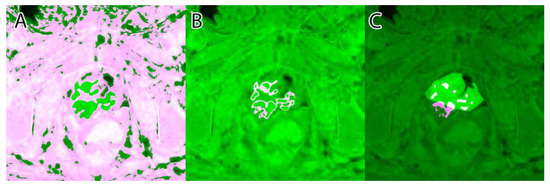

The sixth and final step was to compute the final intensity mask by subtracting the square root from the square sum of the alpha–beta channels and subtracting the resulting value from the luminance. The resulting intensity image can be seen in Figure 2B and Figure 3B. By adding the ‘jet’ color map to it, we obtained a colored intensity map that highlights the tumoral areas, as seen in Figure 2C and Figure 3C.

Figure 2. PI-RADS 2 patient: (A)—T2WI; (B)—ADC; (C)—DWI; (D)—RGB fused image; (E)—grayscale tumor intensity image; (F)—‘jet’-mapped tumor intensity image.

Figure 3. PI-RADS 5 patient: (A)—T2WI; (B)—ADC; (C)—DWI; (D)—RGB fused image; (E)—grayscale tumor intensity image; (F)—‘jet’-mapped tumor intensity image.

Samples of the computed tumor intensity images can be seen in Figure 2 for a PI-RADS 2 patient and in Figure 3 for a PI-RADS 5 patient. Notice the difference in “jet” intensity between the control patient and the patient with extraprostatic invasion.